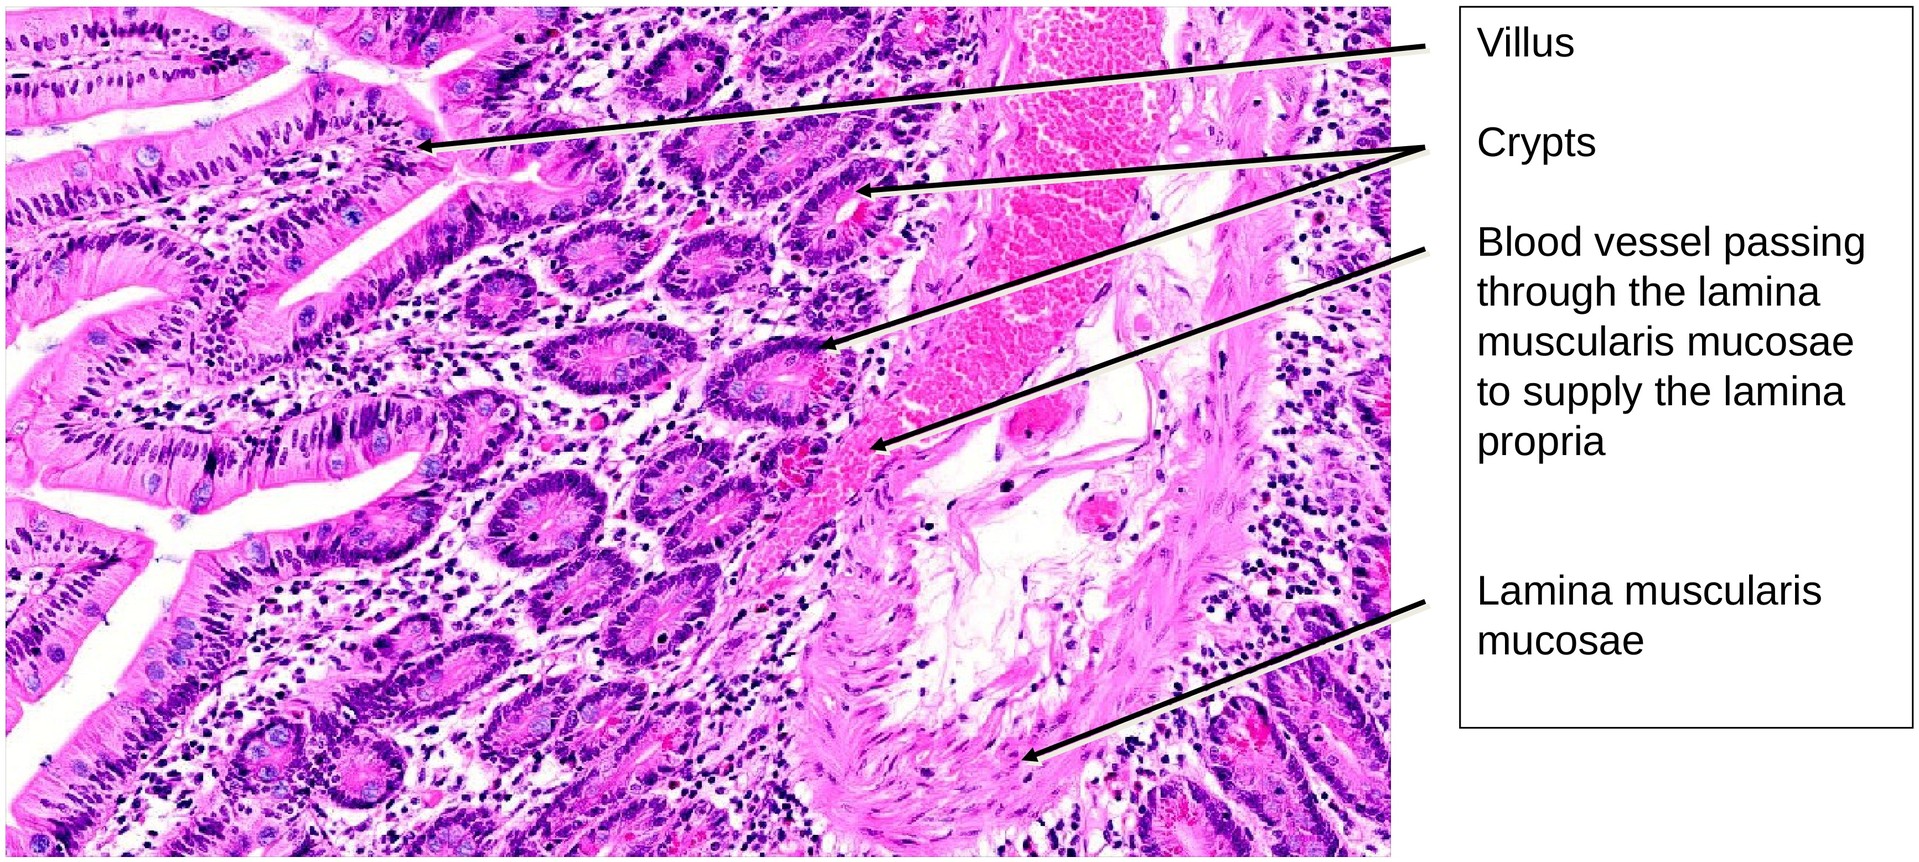

The epithelium is composed of enterocytes (brush-border cells) and goblet cells. The mucosa forms plicae circulares (folds), bearing finger-like villi on their surface. At the base of the intervillar spaces lie the openings of the crypts (crypts of Lieberkühn).

The goblet cells are easily visible even without special staining; in some areas, they appear to have been fixed during mucus secretion.

The lamina propria forms a relatively thin layer beneath the epithelium. The lamina muscularis mucosae is clearly developed; due to the tangential orientation of the section, it appears planar in several areas. Individual smooth muscle cells can be seen extending into the villi, forming the basis of the villus pump mechanism.

Within the crypts, Paneth cells are clearly visible; their apical granules are strongly eosinophilic, giving them a characteristic appearance in H&E staining.